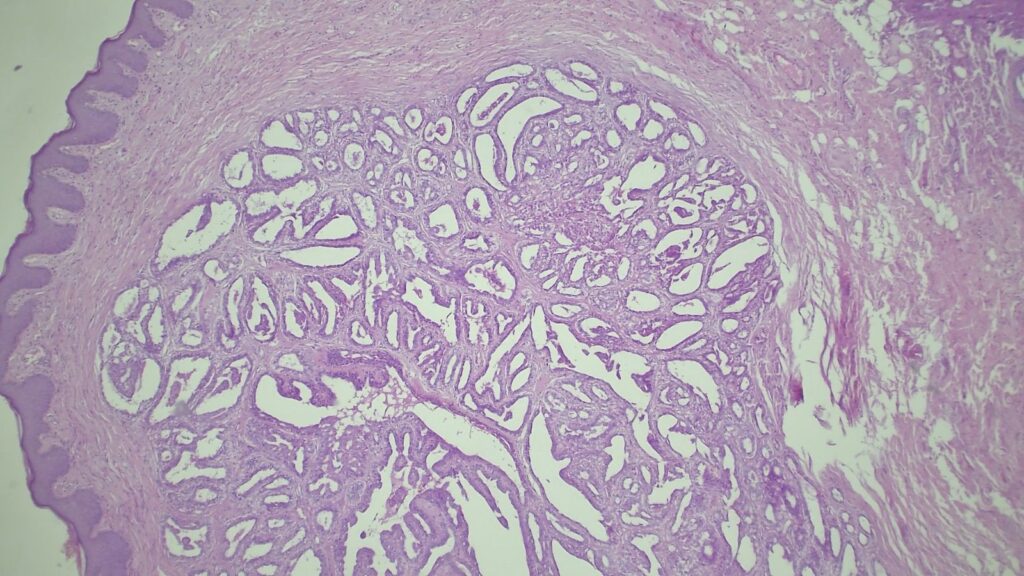

【临床背景:虚惊一场的“高分化腺癌”】 患者: 45岁女性,患有长期慢性肛瘘。 送检疑点: 组织学切片显示,在皮下异常位置出现了一个圆形的腺体增生灶。 考虑到病变的位置和形态,首诊团队和患者都极度恐慌,高度怀疑这可能是在瘘管内继发的高分化腺癌(Well-differentiated adenocarcinoma)。

【病理形态学大解密:寻找良性证据】 仔细阅片后,专家指出了以下几个至关重要的形态学特征(见附带病理切片图):

✅ 腺体发育良好,呈圆形和分叶状结构。 ✅ 边缘虽略不规则,但整体呈推挤性(pushing)和局限性生长。 ✅ 无弥漫性浸润结构。 ✅ 无促结缔组织增生性间质反应(No desmoplastic stromal reaction,这是排除浸润癌的核心点)。 ✅ 细胞学形态温和(Bland cytology)。 ✅ 在慢性炎症和纤维化的背景下,仅见单个典型的核分裂象。 在病变外周,腺体表现出被瘢痕样间质压迫和塑形的特征,而不是破坏性或浸润性生长。